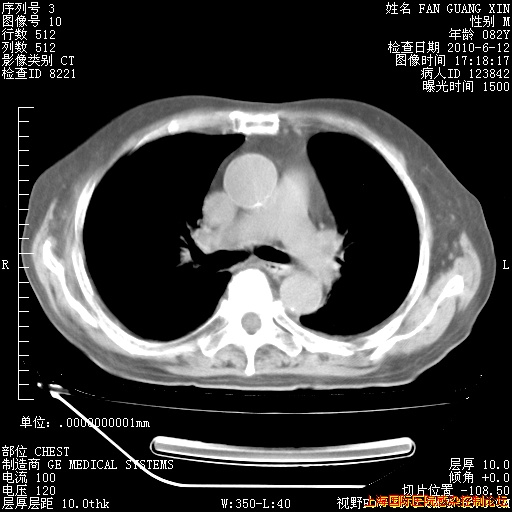

6月12日纵膈窗

今天复查CT

今天CT

整整相隔30天的肺部CT好像有所好转啊。甲强龙减量第3天,需要观察体温。

海管,自昨日你和我通完话后,不知您岳父消化道症状有无缓解?体温怎样?阅读7.12日胸部ct,个人认为目前激素治疗是有效的,甲强龙减量是适宜的。因在抗痨治疗,需密切观察肝功、肾功能和血常规。不过,老年、长期住院和大量使用激素,很担心菌群失调发生